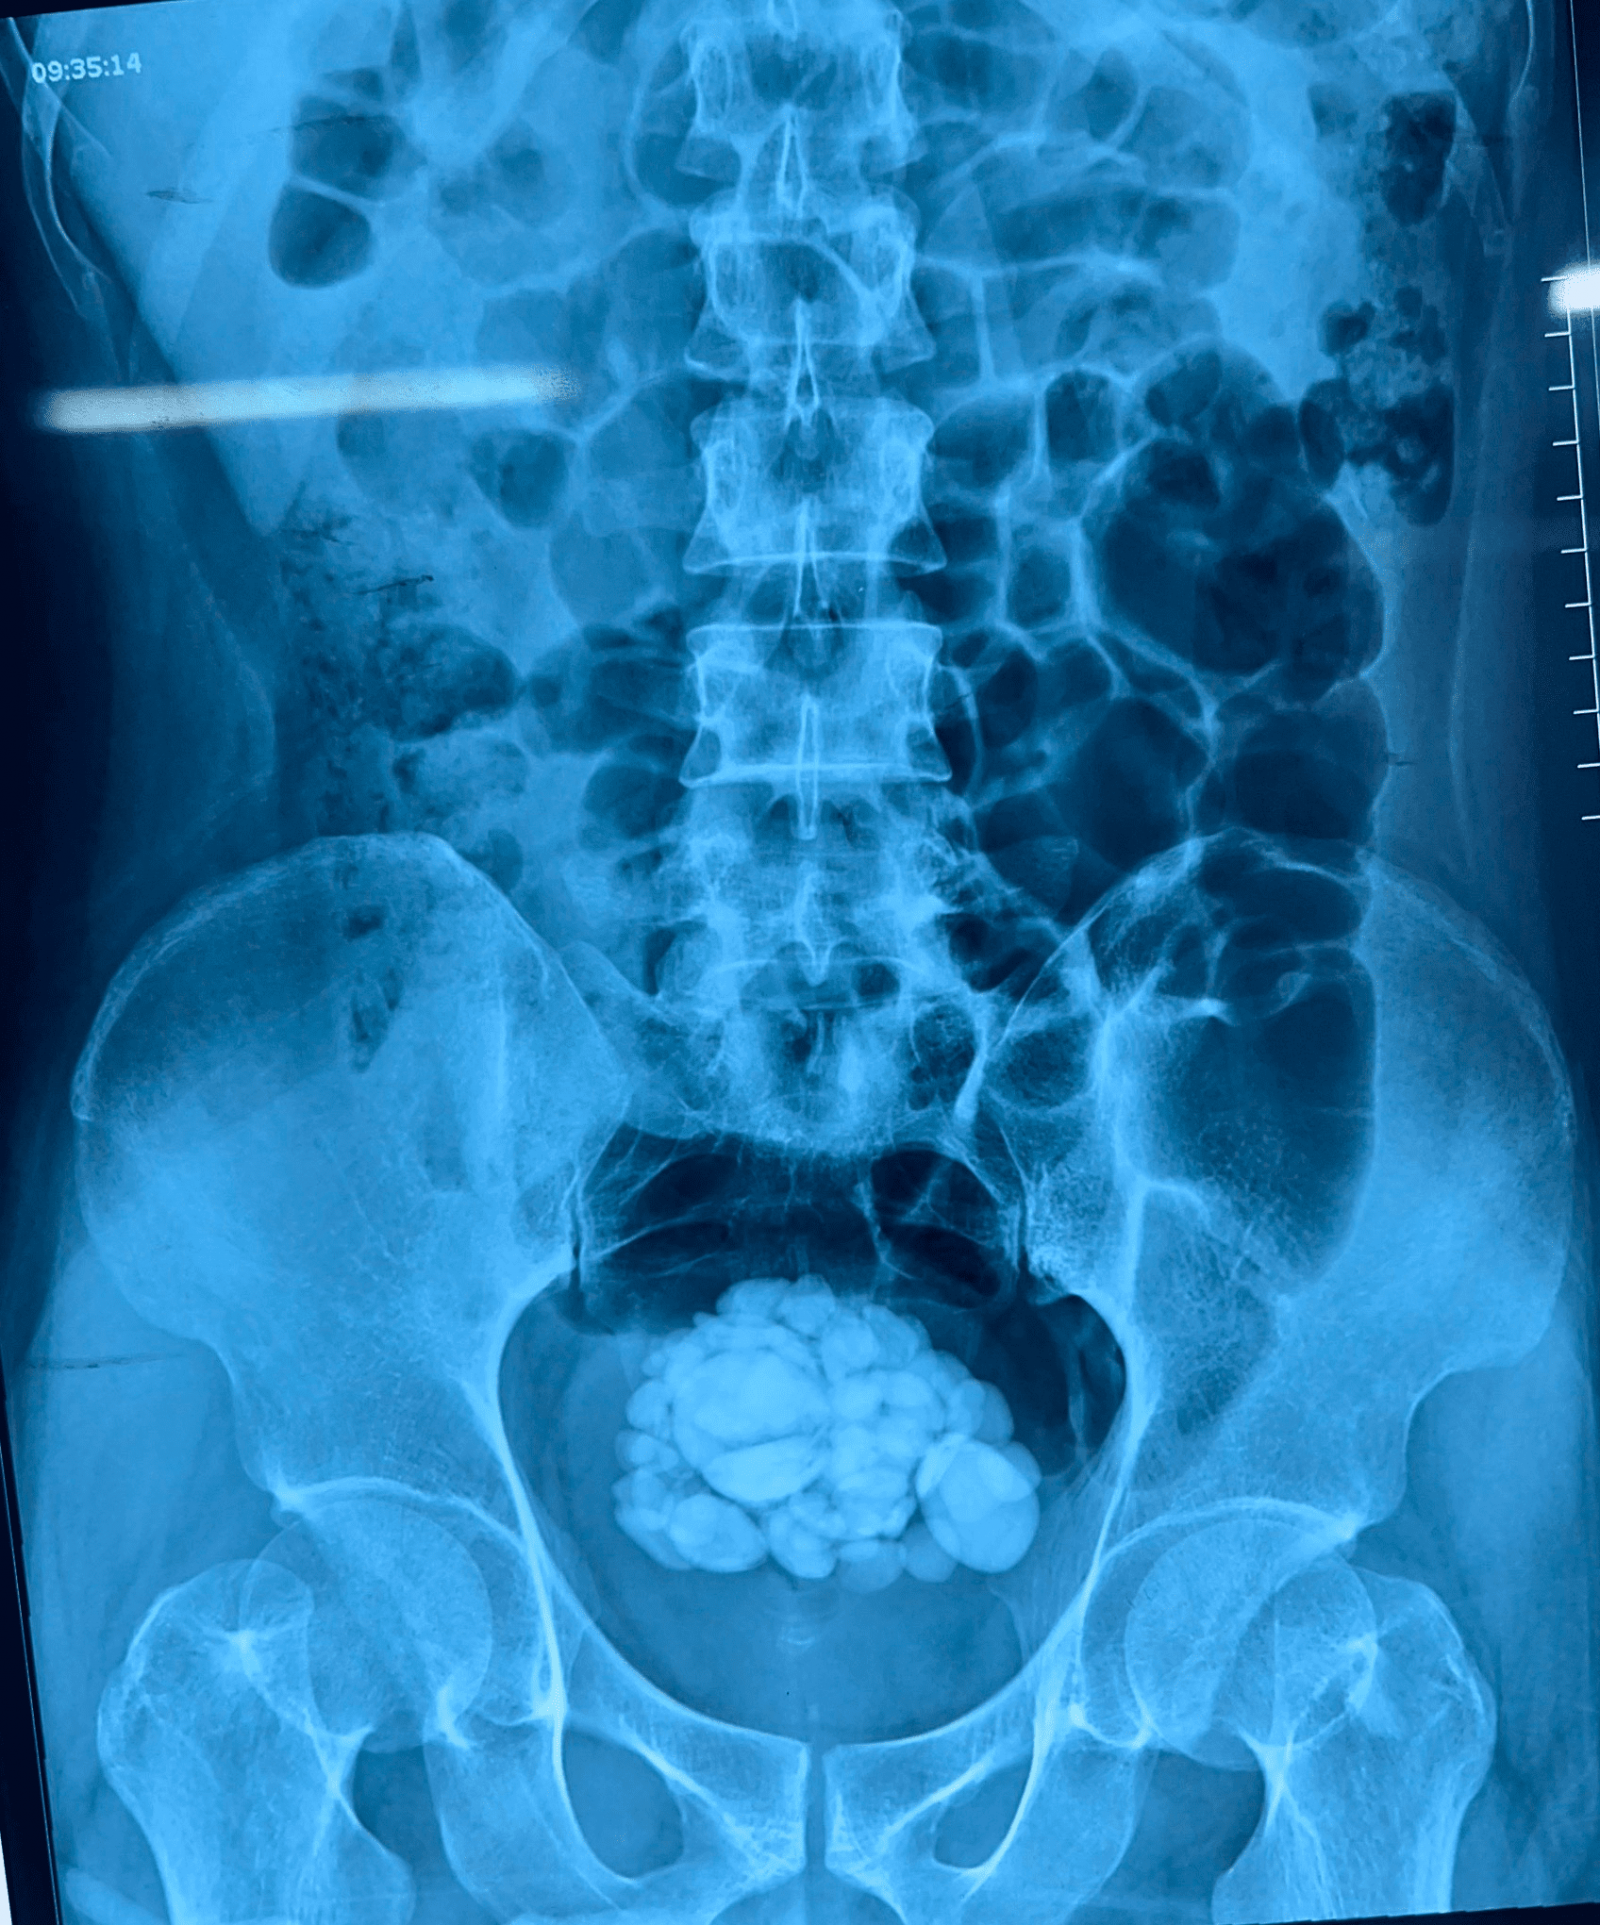

Hình ảnh sỏi bàng quang của bệnh nhân K trước và trong khi phẫu thuật

tại Trung tâm Y tế TP Móng Cái

Ngày 22/12/2021, tại Khoa Ngoại Trung tâm y tế thành phố Móng Cái, đã tiến hành phẫu thuật lấy sỏi bàng quang với nhiều sỏi to nhỏ kích thước đến 4 cm cho người bệnh Hoàng K. 31 tuổi trú tại phường Hải Hòa, TP Móng Cái.

Bệnh nhân có tiền sử chấn thương cột sống, liệt tủy đặt sonde bàng quang thường xuyên, vào viện với biểu hiện tiểu tiện buốt, ngắt quãng và đôi khi có lẫn máu. Sau khi thăm khám và làm các xét nghiệm chẩn đoán trong bàng quang có nhiều sỏi cứng, kích thước to nhỏ khác nhau và được chỉ định phẫu thuật mở bàng quang lấy sỏi.